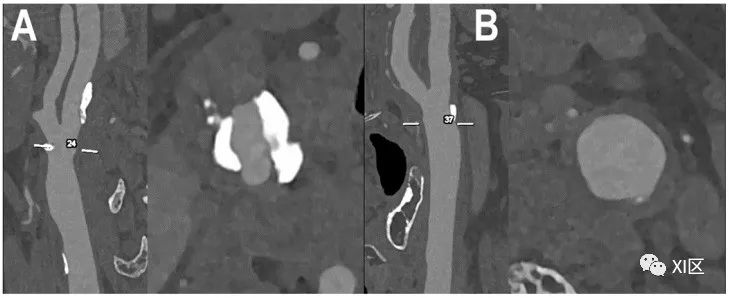

颈动脉分叉的PCCT血管造影:中度混合性和钙化性动脉粥样硬化。PCCT血管造影显示了2个超高清(源数据集;矩阵1024×1024;层厚/增量0.2/0.1mm;体素100 μm;卷积核Bv60;辐射剂量与使用第三代双源CT进行颈动脉血管造影的同等剂量相当)颈动脉分叉处有严重钙化的动脉粥样硬化斑块((A);纵向和轴向视图)和中度/中度混合/钙化斑块((B);纵向和轴向视图)。值得注意的是,(A)中斑块的大块钙化完全分布在动脉壁内,不影响最终管腔狭窄的观察和量化。

颈动脉分叉处的PCCT血管造影:严重混合性动脉粥样硬化。PCCT血管造影显示超高清(源数据集;矩阵1024×1024;层厚/增量0.2/0.1mm;体素100 μm;卷积核Bv60;辐射剂量与使用第三代双源CT的同等颈动脉血管造影相当)颈动脉分叉处有严重的混合性动脉粥样硬化斑块((A):纵向视图;(B):轴向视图)。值得注意的是,无论是相对于剩余的非钙化部分,还是相对于管腔定义,斑块的大块钙化都非常清晰。需要强调的是,成分分析并不局限于原子成分,有证据表明PCCT可进一步用于更好地评估组织成分,神经血管领域以外的其他目标也证明了这一点:例如,骨小梁微结构分析、肾结石的检测和特征描述、乳腺组织特征描述以及痛风中晶体沉积的检测、分化和量化。